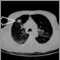

Una TC torácica es una tomografía computarizada del tórax y la porción superior del abdomen.

La tomografía computarizada del tórax puede recomendarse cuando existe la necesidad de examinar las estructuras dentro del tórax. Éste es un procedimiento no invasivo y presenta un riesgo menor que los procedimientos invasivos (tales como una angiografía o una cirugía exploratoria).

Los beneficios de una tomografía computarizada normalmente superan de lejos a los riesgos. Una tomografía es una de las mejores maneras de examinar tejidos blandos, como el corazón y los pulmones.